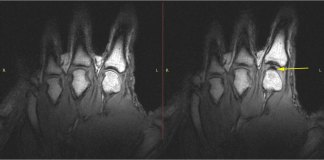

De krakende geluiden afkomstig uit synoviale gewrichten ontstaan tijdens door het optreden van gasvorming wanneer de gewrichtsoppervlakken worden gescheiden. Gregory Kawchuk, een bio-ingenieur en revalidatiegeneeskunde specialist aan de...